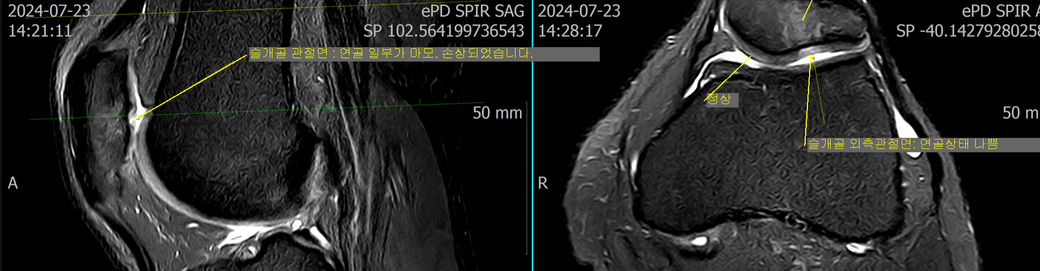

(사진있음)무릎 연골 손상 관련해서 질문드립니다

최근 무릎 통증으로 인해 병원에 방문하여 mri를 촬영하였으며 치료를 위해서 이것저것 알아보고 있는 중입니다.

병원에서는 무릎 슬개골 연골이 손상되었다고 판단하였으며 '연골이 벗겨졌다'라고 말씀하셨습니다.